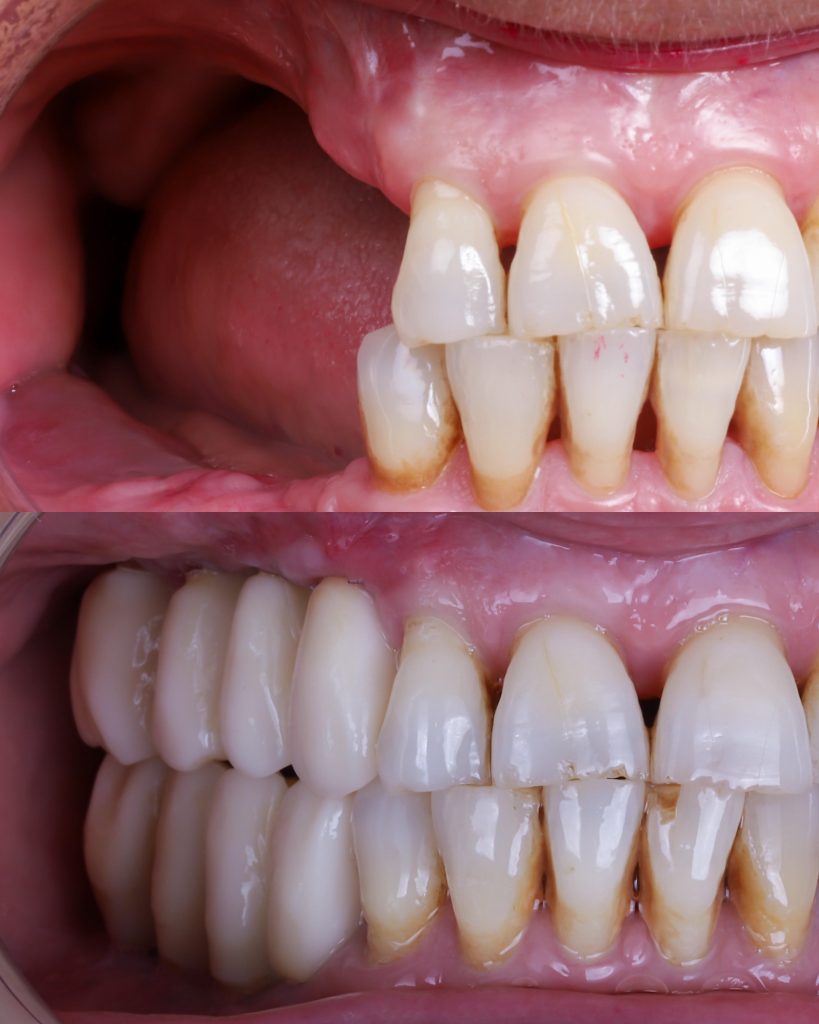

Mas abajo, se puede observar una foto de antes y después de uno de nuestros pacientes con caso de falta de hueso dental severa.

En este caso podemos ver el caso de uno de nuestros pacientes que no tenía hueso dental. Las opiniones de nuestros pacientes son muy positivas.